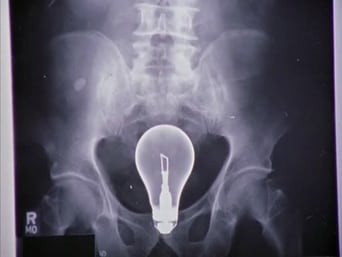

Set in the fictional Sacred Heart hospital in California, John J.D Dorian makes his way through the overwhelming world of medicine, with the help of his best friend, his fellow rookie doctors, and the arrogant, but brilliant attending physician he views as his mentor.

doctor

hospital